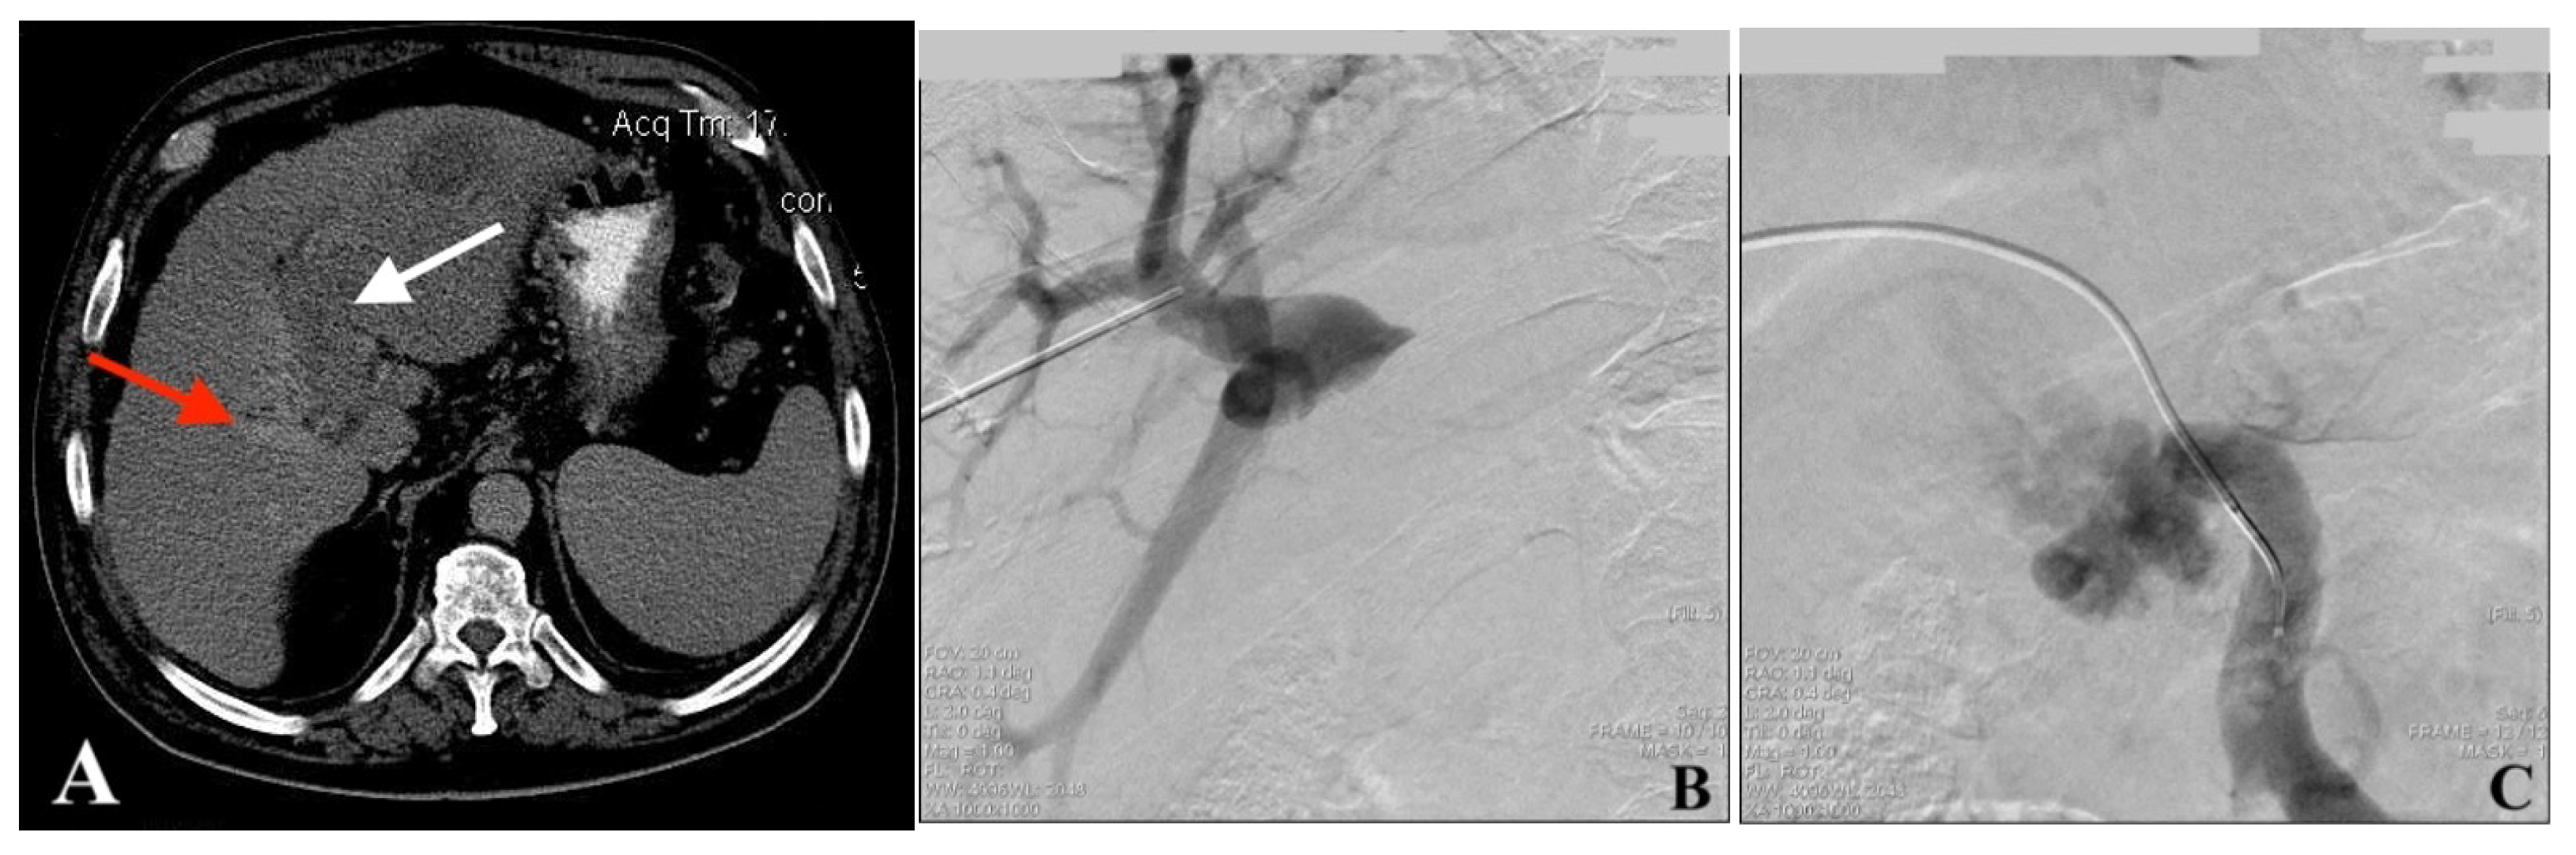

2.4. Portal Vein Access, Venogram, and Recanalization (PVR)

2.5. Endoportal Radiofrequency Ablation

2.6. Portal Vein Stent Placement